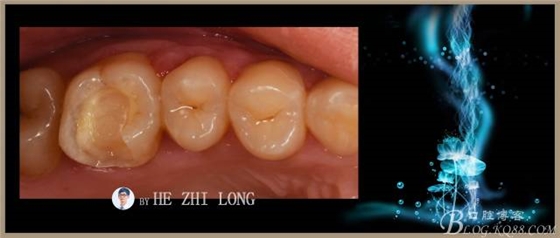

術(shù)后即刻調(diào)合拋光照片:(由于鑄瓷嵌體很難達(dá)到烤瓷嵌體的色澤,因此從牙本質(zhì)到牙釉質(zhì)的色澤沒有很好的過度,稍有點(diǎn)遺憾。)

術(shù)前術(shù)后對(duì)比照片: